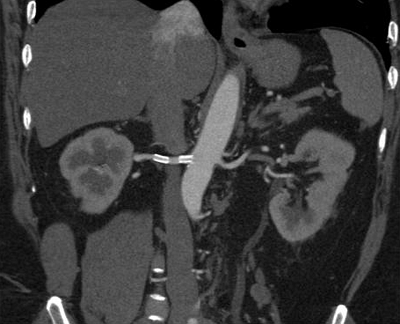

- УЗИ почек и надпочечников;

- УЗИ брахиоцефальных и почечных артерий;

Реноваскулярная гипертензия (5%)

Диагностика

• Резистентная гипертензия, сердечная недостаточность.

• Абдоминальный систоло-диастолический шум, шум над сонными, бедренными артериями.

• Прогрессирующее снижение функции почек (спонтанно или в ответ на ИАПФ).

• Разница длины почек >1.5 см.

• Дуплексная допплерография почечных артерий.

• Магнитно-резонансная 3-мерная ангиография с гадолинием.

• Компьютерная томографическая ангиография.

• Двусторонняя селективная почечная артериография.